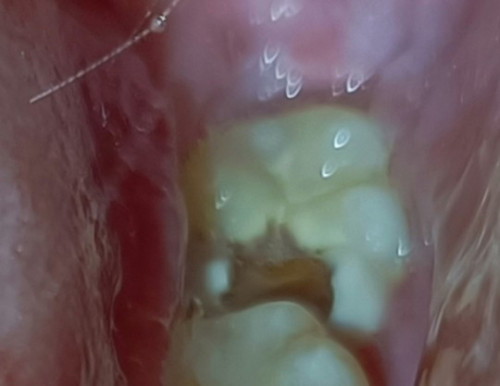

May naka experience na ba nito? Wisdom tooth na kasi nagka tooth decay tapos sobrang sakit nya to the point na nilalagnat nako and di makatulog ng maayos. Naging ganito lang sya nung nagbuntis ako recently kasi 1st weeks ng 1st trimester nakapagpabunot din ako mg ngipin tsaka naka cleaning kasi di ko pa alam na buntis ako nun. Pwede ba tong mabunot? Sobrang sakit kasi talaga. ðŸ˜